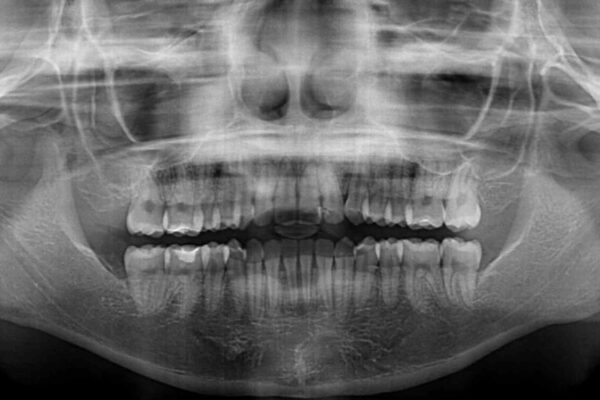

治療前

• 【モニター】短期間で終わりたい ワイヤー装置での非抜歯矯正 治療前画像